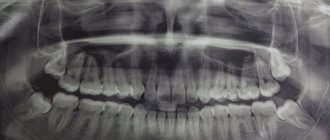

На сегодняшний день, несмотря на современные достижения в стоматологии, курение и имплантация зубов в стоматологии остаются под большим вопросом. Это связано не только с негативным воздействием на организм этой пагубной привычки, но и с постоянным вредным влиянием сигаретного дыма на зубную эмаль и слизистую ротовой полости.

Влияние никотина на зубную эмаль

Негативное воздействие курения на зубную эмаль приводит к тому, что импланты плохо приживаются, а травмированная после этого стоматологического вмешательства слизистая очень медленно заживает. Отрицательное влияние сигарет заключается в следующем:

1. Воздействие высоких температур табачного дыма.

2. Истончение костной ткани из-за влияния на нее смол и никотина.

3. Снижение иммунитета.

4. Образование зубного камня и желтого налета.

Если часто курить, влияние высоких температур приводит к тому, что зубная эмаль со временем истончается, становится хрупкой и ломкой.

Истончение костной структуры значительно увеличивает риск выпадения имплантата и его отторжения. Снижение иммунитета приводит к частым воспалительным заболеваниям ротовой полости, вплоть до остеомиелита, который является частым спутником людей с длительным стажем курения. Это делает практически невозможной качественную постановку импланта.

Зубной камень и плотный налет, которые возникают, если часто курить, являются прекрасной средой для размножения бактерий, которые, в свою очередь, негативно сказываются на состоянии костной системы и мягких тканей полости рта.